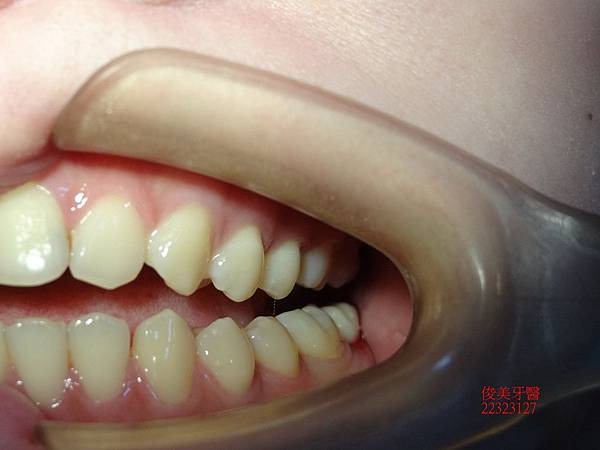

裝牙齒囉!!患者非常高興,除了解除牙痛的困擾,也在重建過程中,舒適少痛。